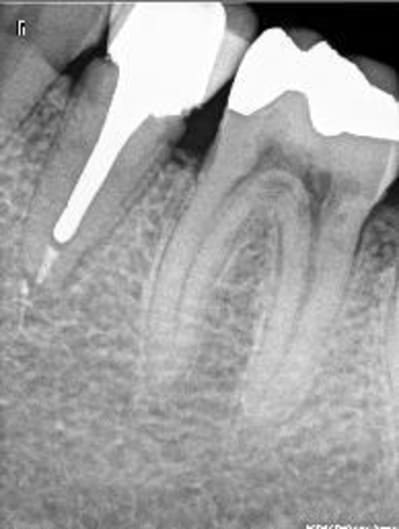

Mon patient vient de partir.

J'ai repris une radio.

Il a eu un peu mal durant la semaine mais moins.

Cependant, quand j'ai appuyé sur la racine, plus de douleurs vives, légère gene decrite par le patient.

Quand j'ai réintroduis l'inlay core, gène, douleur legère mais pas aussi brutale qu'avant.

Donc en faveur d'une desmodontite en passe de guerrir.

Cependant, du sang et meme un liquide purulent remonte du canal.

Quand j'ai passé un instrument, j'ai cherché la gutta pour voir mais je n'ai remonté que des petites boules de sang coagulée, un peu malodorante.

Mais pas de sensibilité du tout quand je passe linstrument (ct une lime 25)

Moi ce que çà m'évoque c'est une possible perforation de la racine par le tenon dans le sens vestibulo-lingual. Vu la longueur du tenon c'est possible. Le tenon a-t-il un axe bizarre ? Un saignement dans le canal c'est pas bon signe.

Si le sondage est normal, la palpation de la table osseuse du côté où la racine est fenestrée devrait être sensible.

La douleur lors de l'insertion du tenon est caractéristique d'une telle lésion.